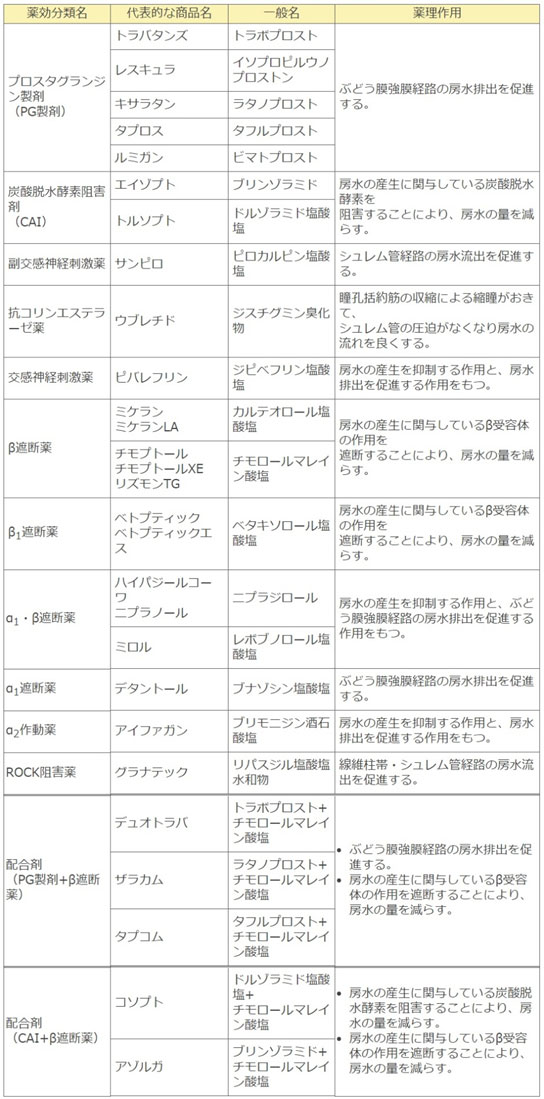

えのき眼科で行われている緑内障治療1 点眼治療

まずは眼圧を下降させることが治療の基本です。

などを組み合わせて、目標眼圧に向けて点眼治療を行います。